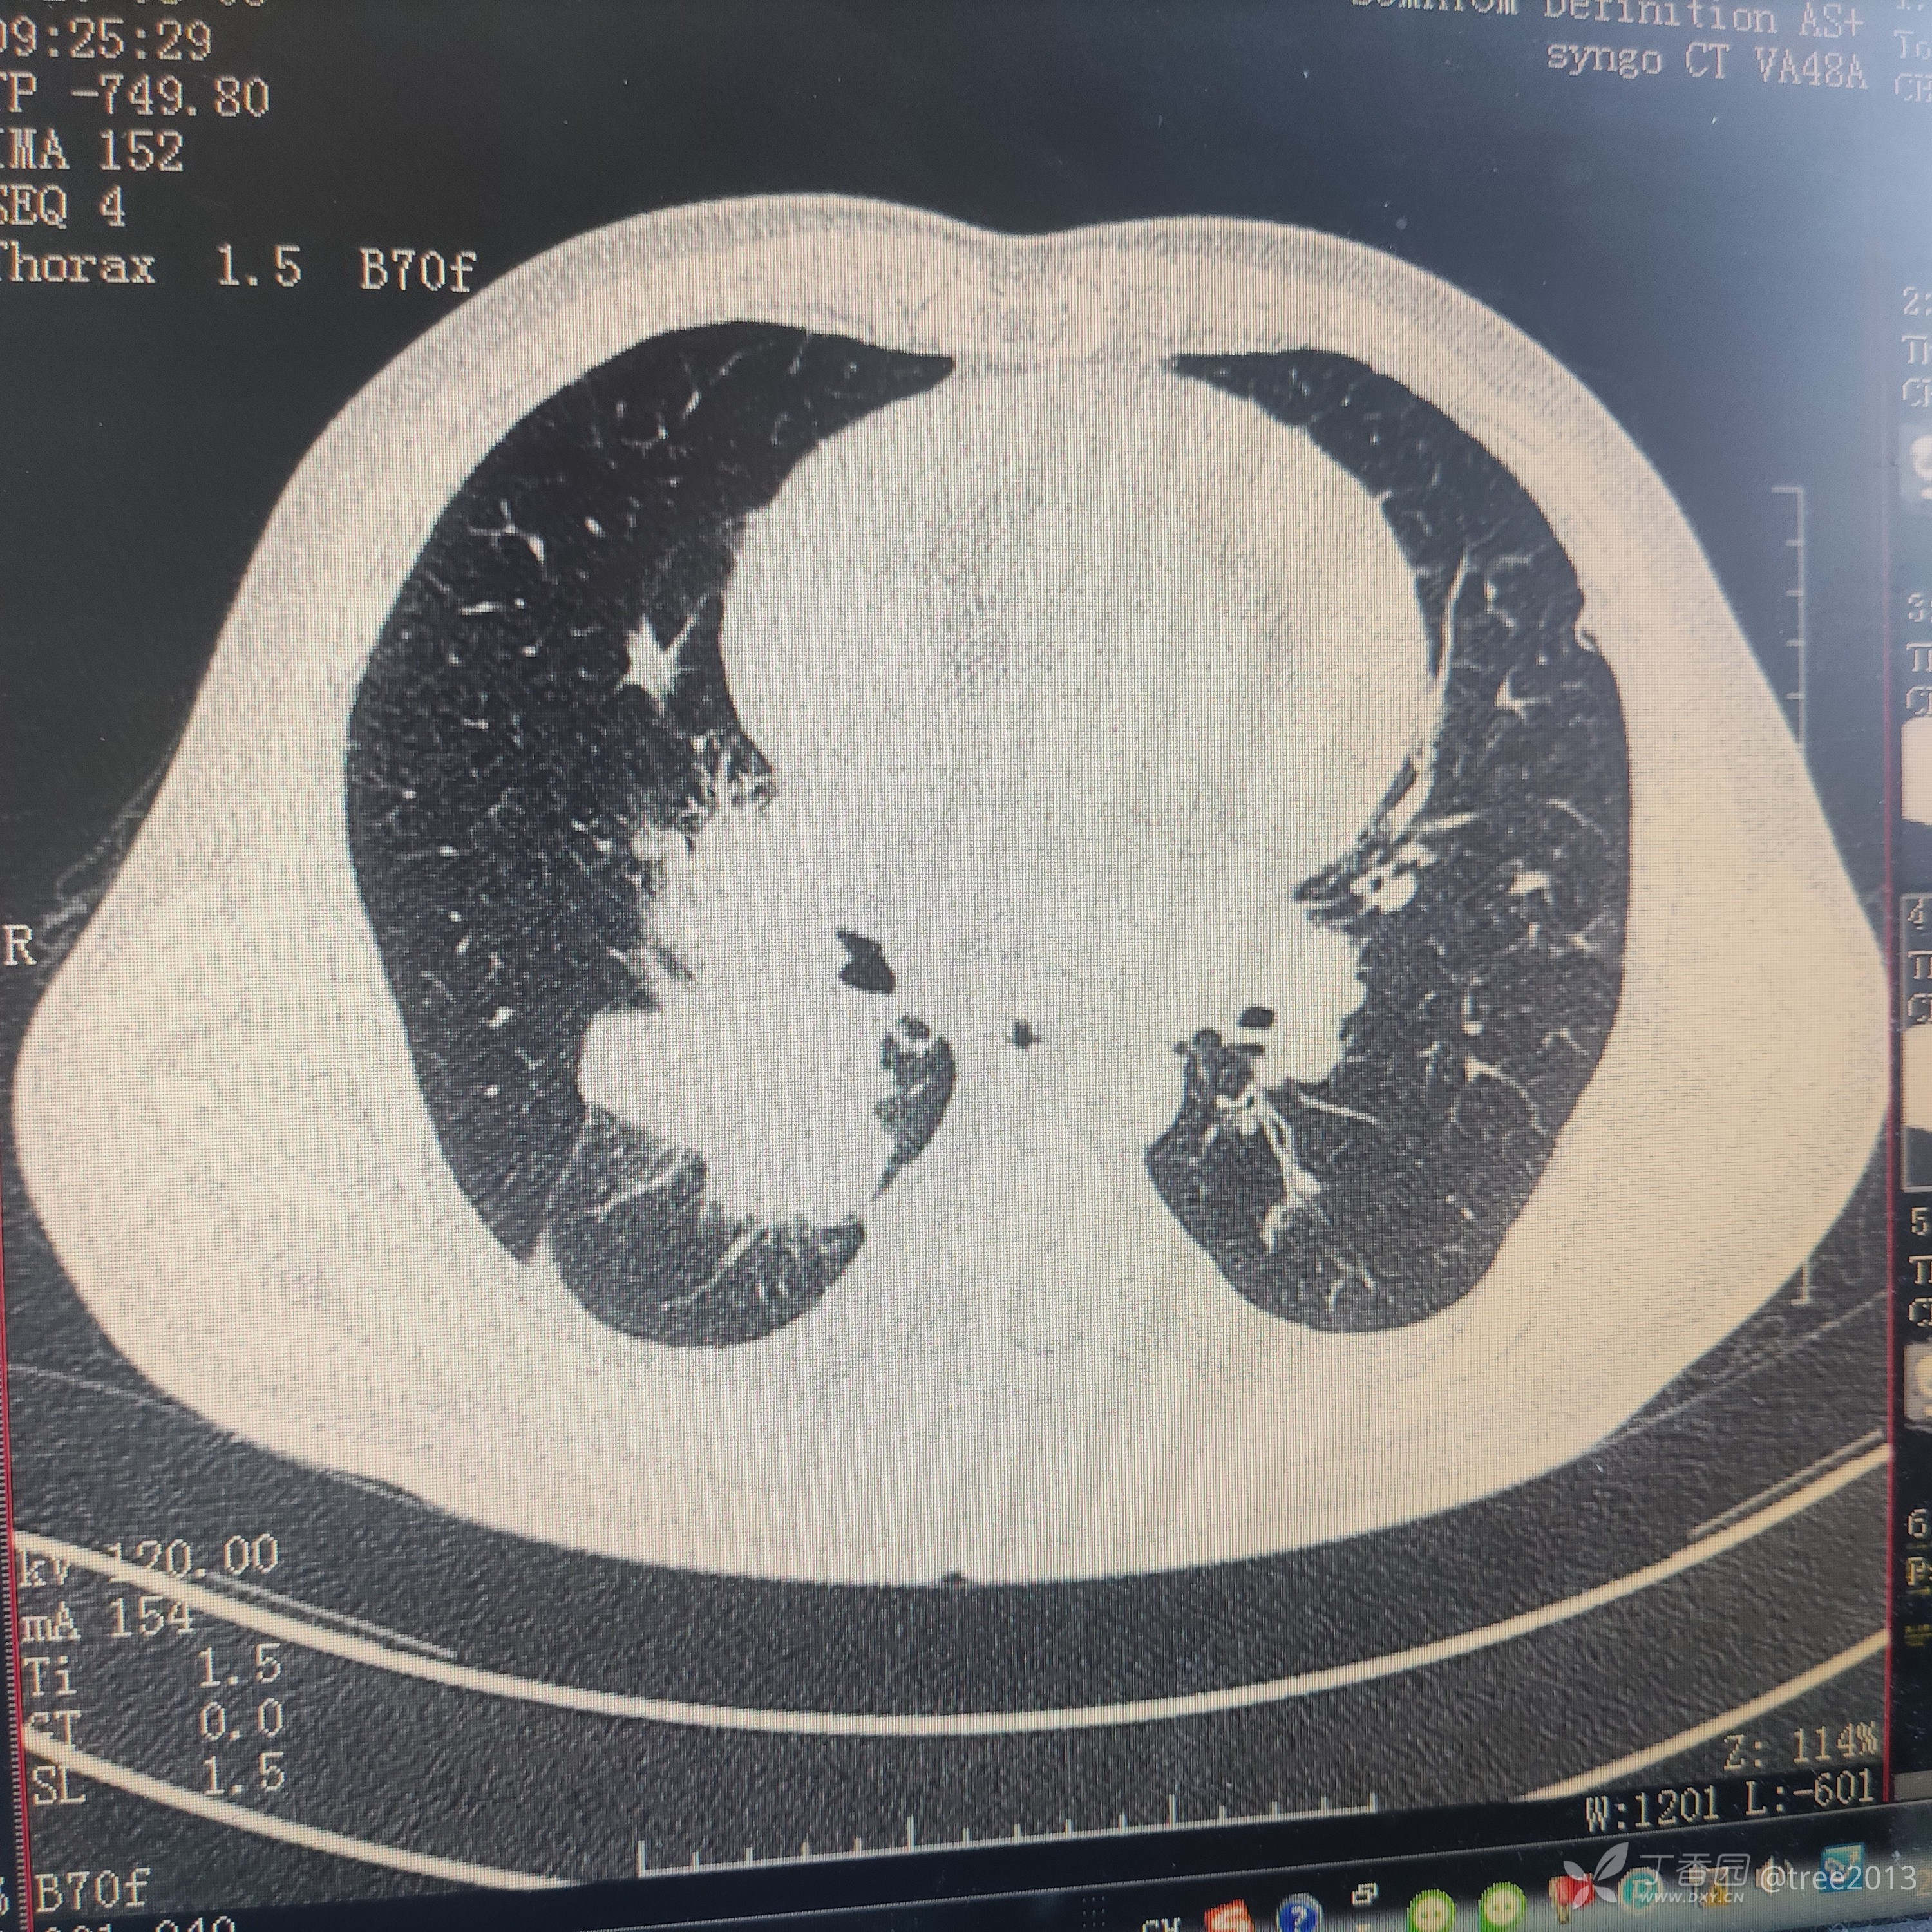

胸部CT:

诊断:肺部恶性肿瘤伴多大转移 心包积液 胸腔积液